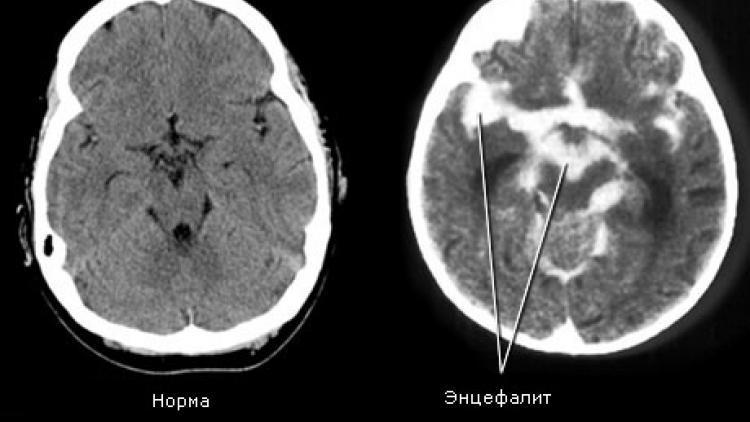

В анализе крови обнаруживается высокое количество лейкоцитов, скорость оседания эритроцитов увеличивается. Фиксируется эпилептическая деятельность. Во время проведения магниторезонансной томографии регистрируются патологические изменения головного мозга. При исследовании глазного дна определяются застойные явления зрительного нерва.

Диагностика энцефалита головного мозга обычно включает в себя неврологическое обследование, анализ крови и спинномозговой жидкости на наличие вирусов или антител, компьютерную томографию (КТ) или магнитно-резонансную томографию (МРТ) головного мозга.